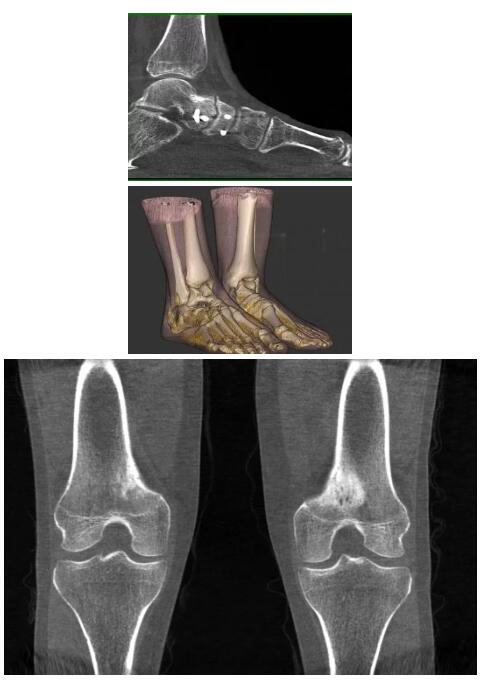

另外一款被稱為世界上最小的CT,它的重量僅300磅,不僅能夠掃查足部,還可以檢查膝蓋和上肢等。

與上面介紹的CT一樣,它同樣具有輻射低、占地空間小(23*36)的特點(diǎn),隨開隨用(支持直接接入墻上的插座)。

這款CT使用非常方便,通過上下移動保持與患者的手臂或者雙腿齊平,掃描快速,僅需要30秒左右就可以完成掃查。

以下是這些“特立獨(dú)行”的CT所拍出來的圖像: